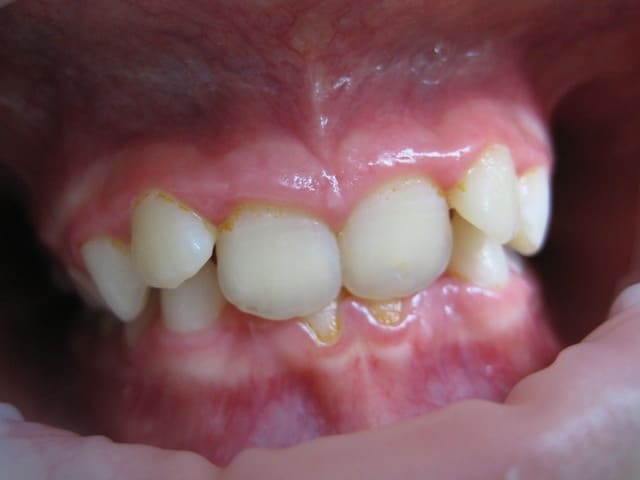

Je suis entrain de faire une observation clinique d'une patiente de 10 ans.

Elle présente une linguo-version et une égression des incisives maxillaires et mandibulaires. Le truc c'est que les racines de 11 et 21 semblent bien positonnées sur la télé de profil, alors que les faces vestibulaires sont très lingualées.

C'est une Cl II/2 non ?

Je ne sais pas si ta question est sérieuse? Tu fais l'analyse céphalo, les photos et tu te poses la question quoi faire? C'est une classeII 2.Si tu ne fais pas de l'ortho, adresse car c'est le bon moment pour traiter et dévérouiller. Quant à la dévitalisation j'espère que c'était de l'humour.

Jeamba, je me demandais que faire uniquement par rapport à l'angulation entre les axes radiculaire et coronaire des incisives. Pour le reste j'ai vu que c’était une classe II2